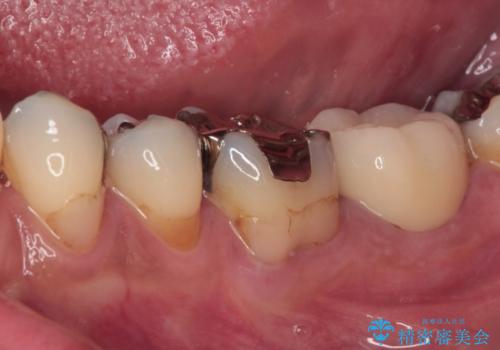

神経組織を部分的に除去することが分かっていたため、ラバーダムなどの環境を整え、無菌的環境下にて処置を進めて行きました。

虫歯は深くまで進行しており、歯冠部の神経から出血が認められました。神経を部分的に除去したところ出血が治まったので、生体親和性の非常に高いセメントにて充填し、仮封をしました。

後日状態を確認したところ、残された神経に異常は認められませんでした。